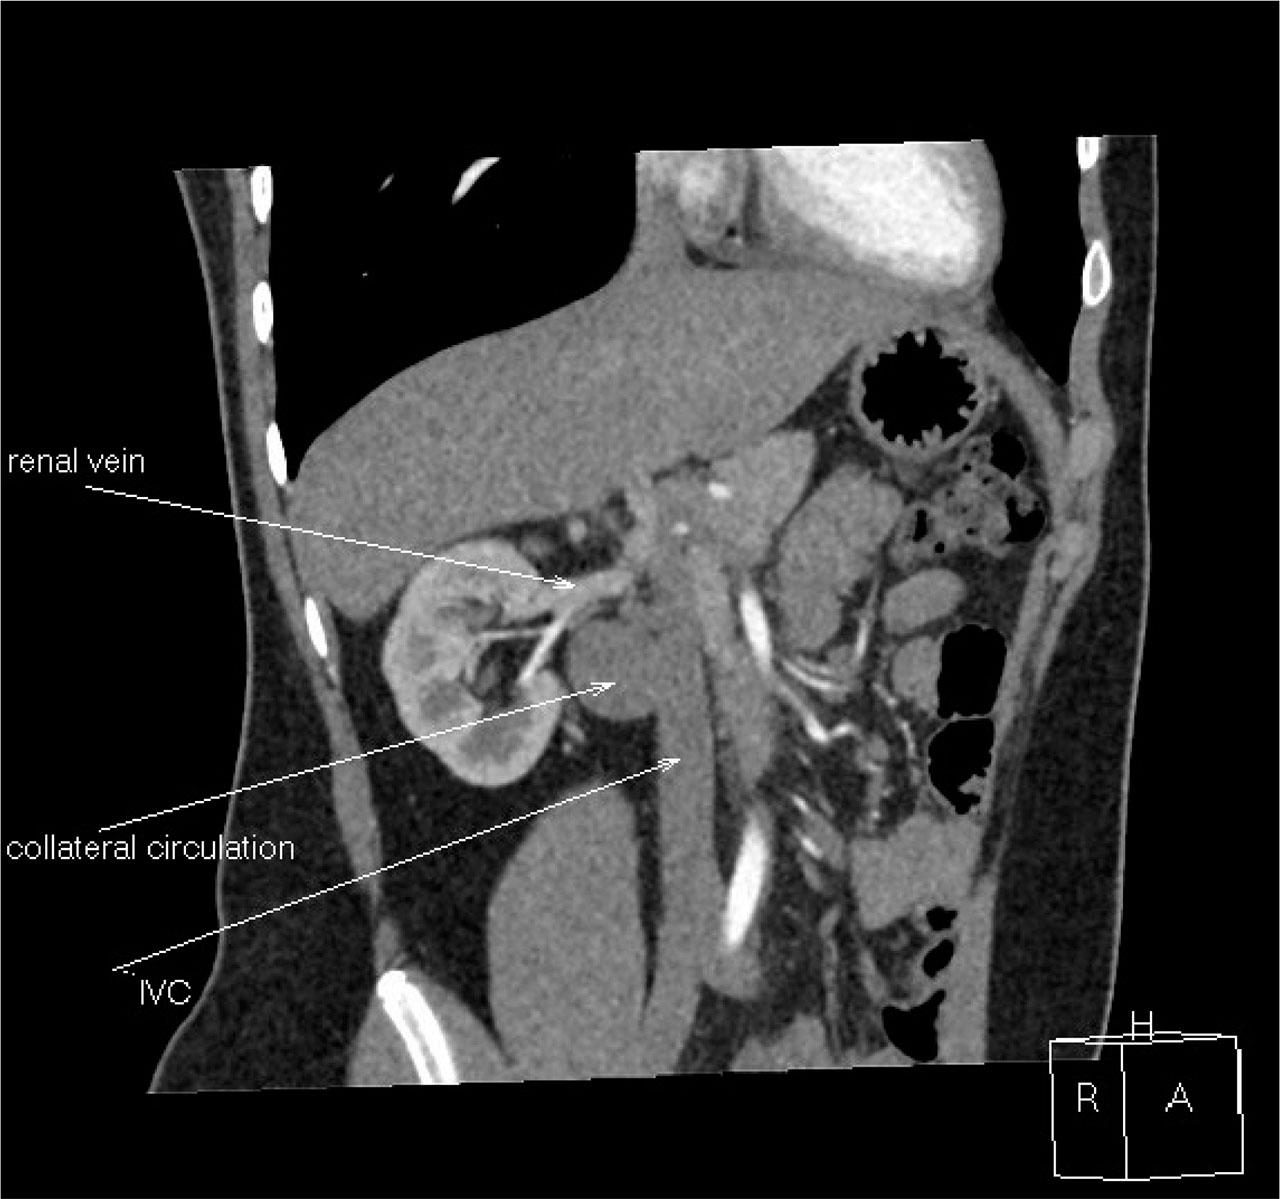

Figure 2.